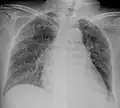

Tuberculosis of the lungs

A case of miliary tuberculosis in an 82-year-old woman: